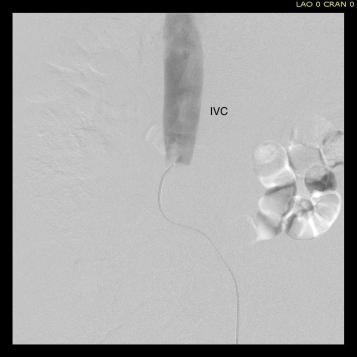

Once the wire crossed into the iliac vein from above, it was captured and brought out. While ballooning by itself is inadequate for revascularization, it greatly eases wire capture and on the right, it was done simply by driving the wire from above into the sheath. Wire capture wins access across the iliocaval and IVC filter occlusion from below.

Once wire access is done, ballooning across the filter is done from both sides. A large sheath is them delivered across the IVC filter. Finally, a Palmaz stent mounted on a large balloon is delivered and deployed. I chose to do this from the right access, and retracted the wire on the left -something done with some trepidation because of the great difficulty gaining this access, but with with prior balloon dilatation, reaccess is made easier. Also, plan B would be reaccess from above.

When this is accomplished, the left sided wire is reaccessed across this stent. This is the venous side analogue to gate access in EVAR (below).